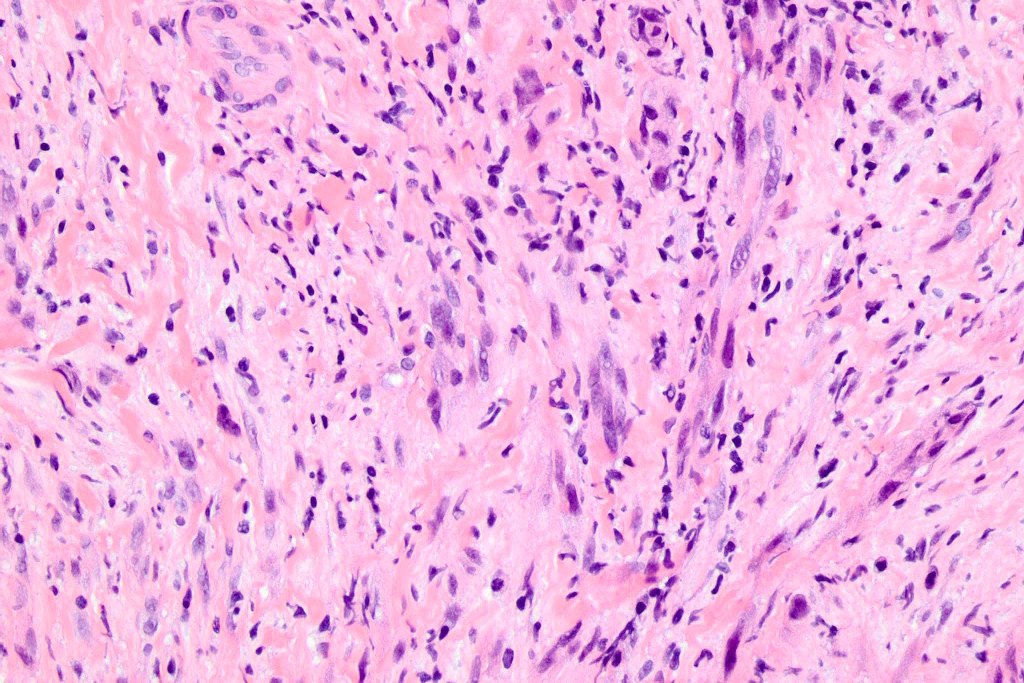

•Paucicellular spindle cell infiltrate with “myxoid” fine to a dense collagenous stroma

•Hyperchromatic nuclei

•Variable pleomorphism

•Mixed desmoplastic & spindle cell variant (10%)